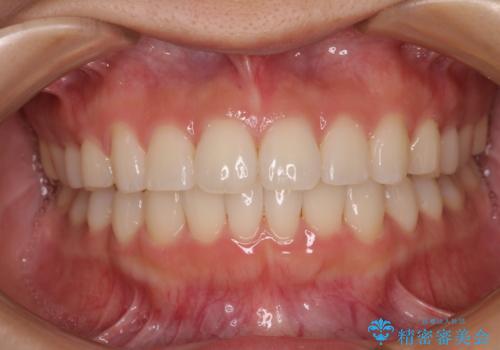

上下前歯のデコボコ ワイヤー装置で楽して改善

治療中は大きなトラブルもなく、予定の1年半でスムーズに治療を終えることができました。